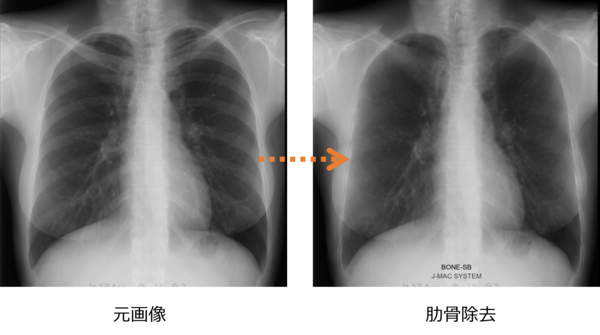

(1) 肋骨陰影の減弱

撮影した画像データから,AIを用いて肋骨の陰影を薄くする画像処理(減弱)を行うことで病変を見つけやすくしたり,骨に隠れて見えない異変の見落としを防止したりするなど医師の読影をサポートする。

新機能イメージ